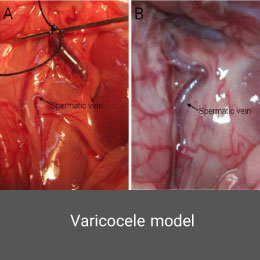

- Create and induce a variety of animal models